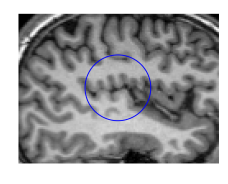

We now show numerical examples and compare our results with those in Li et al. [7] using the level set method. To be consistent with the code of [7] from http://www.imagecomputing.org/~cmli/code/, we use the two-dimensional Gaussian low-pass filter instead of the Gaussian kernel to avoid specifying the domain size of . The filter can be generated by the MATLAB’s fspecial function. Figure 4 displays several numerical experiments on different intensity-inhomogeneous images. In all five experiments, we set . In Figure 4, from left to right, we set , , , , and . In the table in Figure 4, we compare the ICTM and the level-set method in Li et al. [7] in terms of the number of iterations for convergence. In the first example from the left, the method in Li et al. [7] does not even converge. In all other examples, ICTM converges in significantly fewer iterations, demonstrating its very high efficiency.